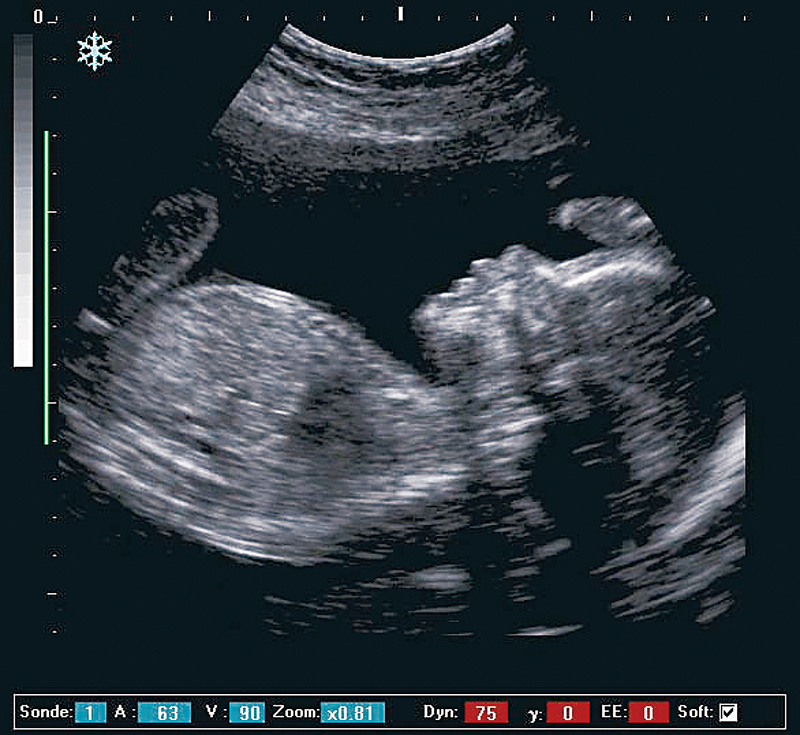

耳では聞こえない高い周波数の音波を用いて、体の中の情報を得る方法について研究しています。病院では、超音波診断装置を用いた診断が日常的に行われていますが、次世代の診断装置の基礎を築のが研究のメインテーマです。また、音波による生体組織診断のための、超音波顕微鏡についても研究しています。この分野の研究には、ハードウェアからソフトウェアにわたる幅広い知識が必要ですが、だからこそおもしろいのです。